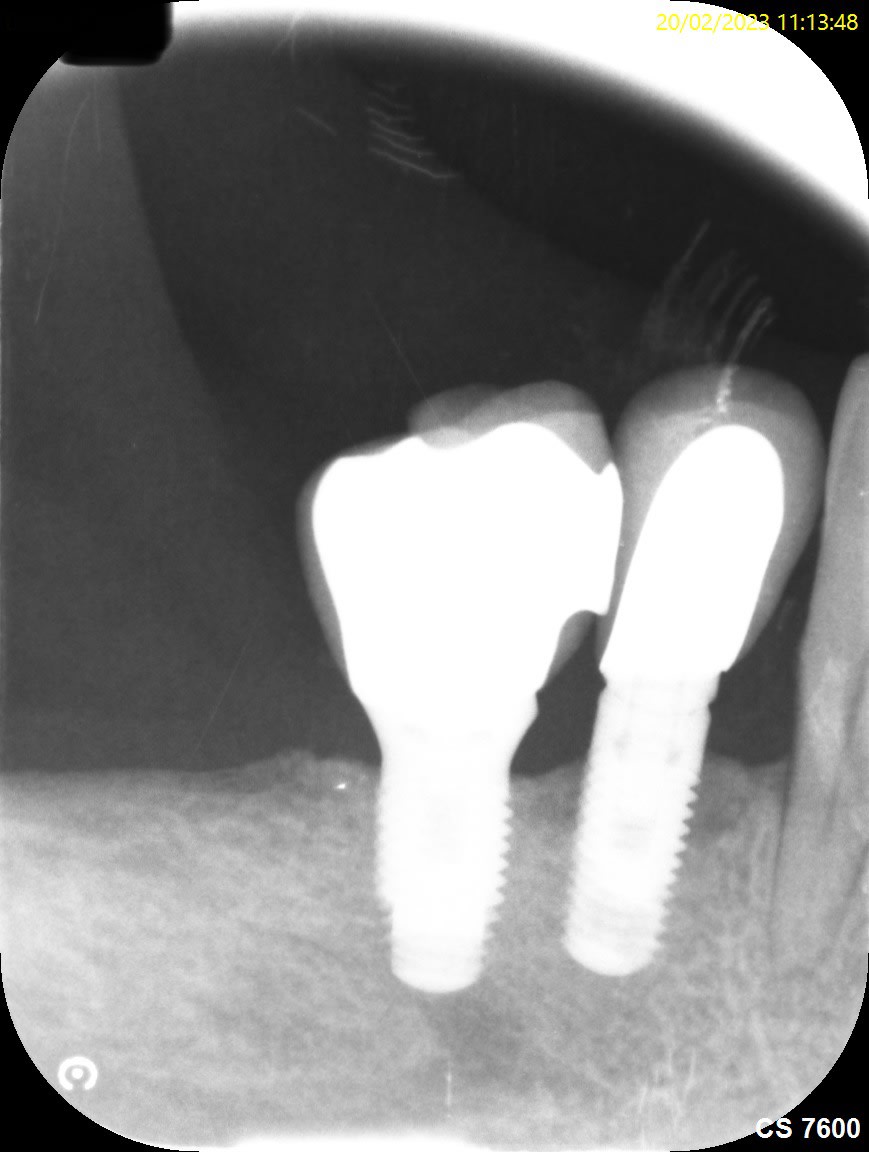

Bonsoir pourriez vous m’aider pour la marque de ces implants je pense à du zimmer tsv pour les implants en position de 4…je pense que les implants distaux sont des zimmer aussi car posé par le même praticien mais j’ai l’impression que ce sont des tissus level est ce que la connectique est identique?

Pour les premo c’est des TSV, et les molaires des AdVent zimmer pour les 2….

Connexion différente, hex interne pour les TSV, octogonale comme des straumann pour les AdVent